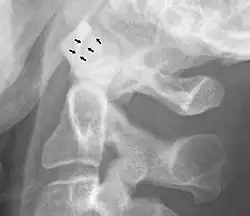

Normal atlanto-dental joint on projectional radiography.

A widening of the atlanto-axial joint, as measured between the posterior surface of the anterior arch of atlas and the front of the odontoid process, indicates an injury to the transverse atlantal ligament.[6] Normally, this atlanto-dental distance is less than 2 mm, sometimes a maximum of 3 mm is accepted in men and 2.5 mm in women.[6]